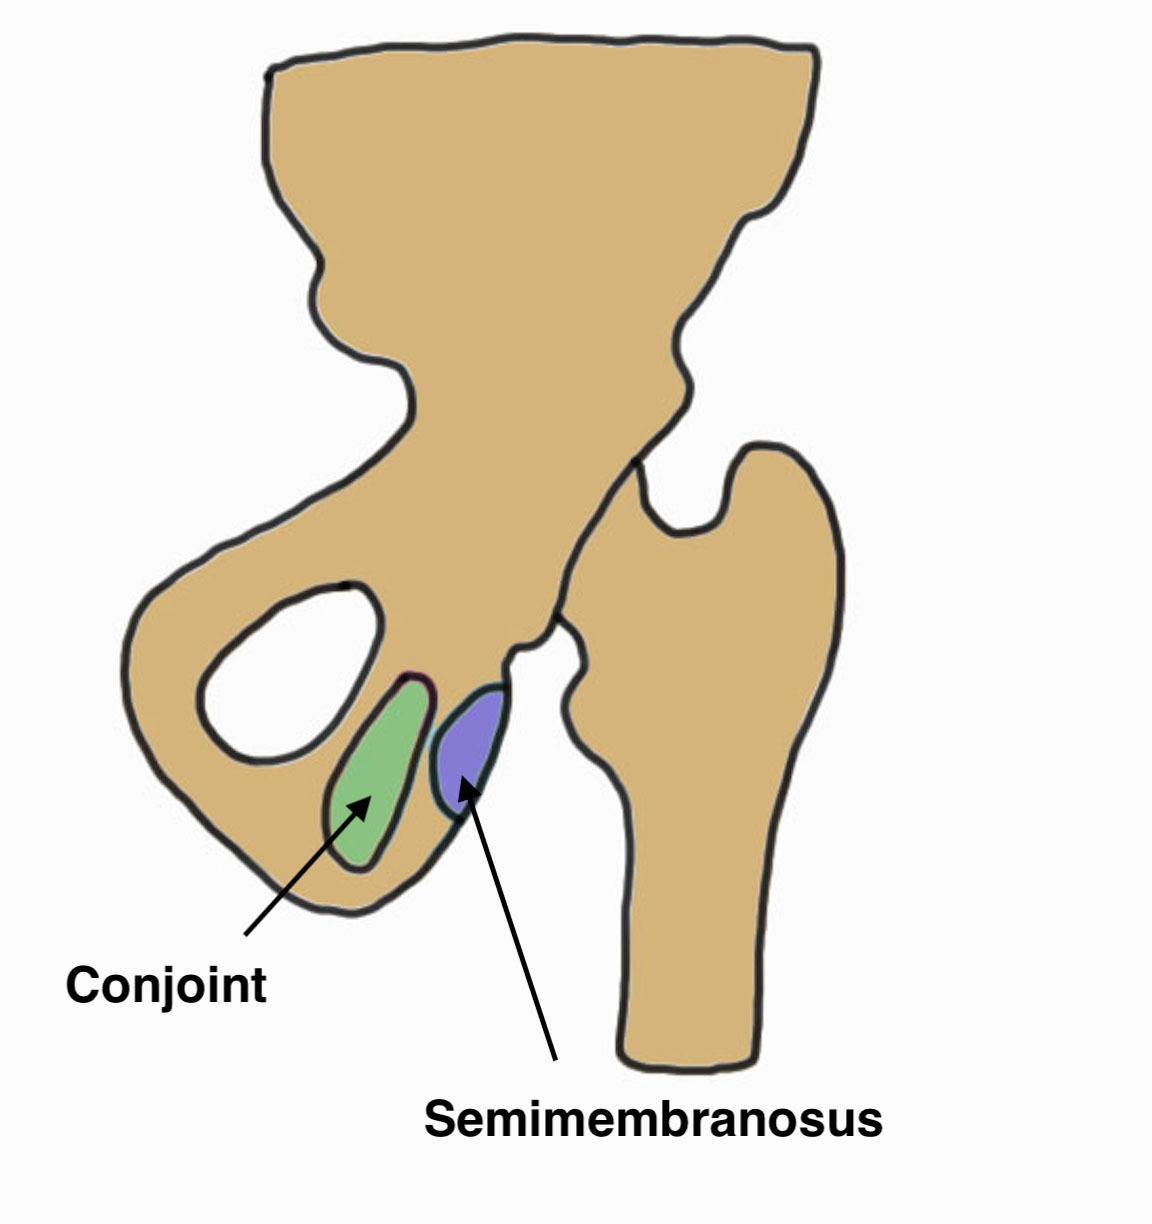

Anatomy

Hamstring by definition originate from the (lateral aspect of) the ischial tuberosity

Conjoint tendon

- biceps femoris and semitendinosus

- posterolateral aspect of the ischial tuberosity

Semimembranosus

- separate attachment

- anterolateral aspect of the ischial tuberosity